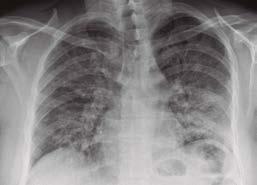

Las radiografías de tórax muestran opacidades pulmonares difusas (ver figura 3: una Rx de tórax con opacidades pulmonares bilaterales). La mayoría de los pacientes han requerido hospitalización, frecuentemente en cuidado intensivo y algunos de ellos necesitaron ventilación mecánica; siete de estos pacientes fallecieron. Aunque no se ha identificado un producto o sustancia única que explique todos los casos, la gran mayoría de pacientes reportaron el consumo de líquidos con productos de marihuana, ya sea sola o en combinación con nicotina; ha llamado especialmente la atención, el alto contenido de acetato de vitamina E presente en los líquidos que contienen productos de la marihuana, pero aún no se puede establecer una relación causal. A pesar de que es claro que se trata de un síndrome clínico nuevo, relacionado con el vapeo, no se ha podido establecer la causa específica del problema.

Figura 3